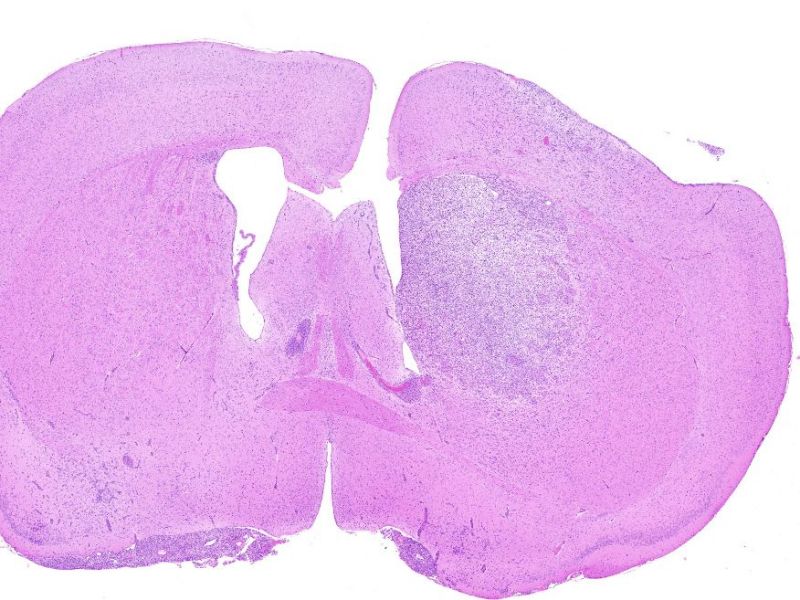

脑缺血动物模型